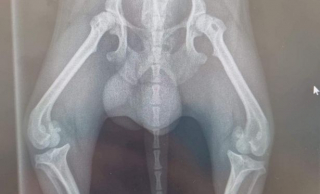

Les genoux de Jerry sont très abîmés

A force de négligence, Jerry, le petit Chihuahua, s’est blessé. Ne recevant aucun soin de la part de son ancien propriétaire, les blessures de Jerry se sont aggravées. Lorsqu’il est arrivé au refuge de la RSPCA Cornwall, les soigneurs devinent immédiatement qu’une intervention chirurgicale sera nécessaire pour ses deux pattes arrière. S’ils n’interviennent pas, le petit chien risquera de ne plus pouvoir marcher.

©RSPCA Cornwall Branch / Facebook